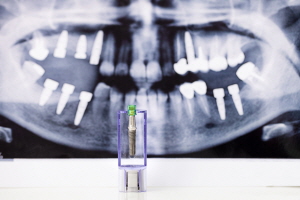

- 픽스쳐(고정체): 임플란트의 뿌리 역할을 하며, 잇몸뼈에 고정됩니다.

각 부위에 어떤 재료가 사용되느냐에 따라 가격이 달라집니다. 예를 들어, 보철물은 금속 또는 세라믹으로 만들 수 있고, 픽스쳐는 티타늄 또는 지르코니아 같은 재료를 사용할 수 있습니다.

추가적인 뼈이식 비용

임플란트 시술을 위해서는 튼튼한 잇몸뼈가 필수적입니다. 하지만 나이가 들거나 치아를 상실한 지 오래된 분들의 경우 잇몸뼈가 약해져 임플란트 시술이 어려울 수 있는데요, 이러한 경우 뼈이식이 필요합니다.

뼈이식은 부족한 잇몸뼈를 보충해 임플란트가 안정적으로 자리잡을 수 있게 도와주는 과정입니다. 이 뼈이식재 또한 일종의 재료비이기 때문에, 임플란트 비용에 추가로 반영됩니다.